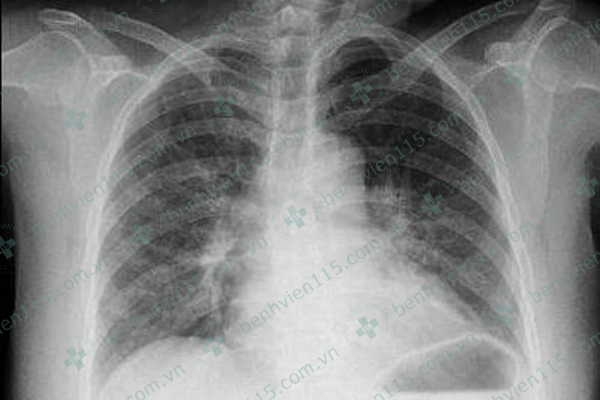

Ảnh X-quang tim phổi thẳng: Lồng ngực cân đối, thành ngực dày trung bình, không ghi nhận tụ dịch lớn trong thành ngực, xương sườn hình dạng bình thường, không ghi nhận nứt gãy, thâm nhiễm rải rác hai rốn phổi, bóng tim to. |

Tại Khoa Tim mạch Tổng quát xác định bệnh nhân bị nhồi máu cơ tim cấp chênh lên vùng trước rộng. Sau đó, bác sĩ đã điều trị tích cực, bệnh nhân đã giảm khó thở bớt đau ngực, sinh hiệu ổn định và tim đều trở lại.